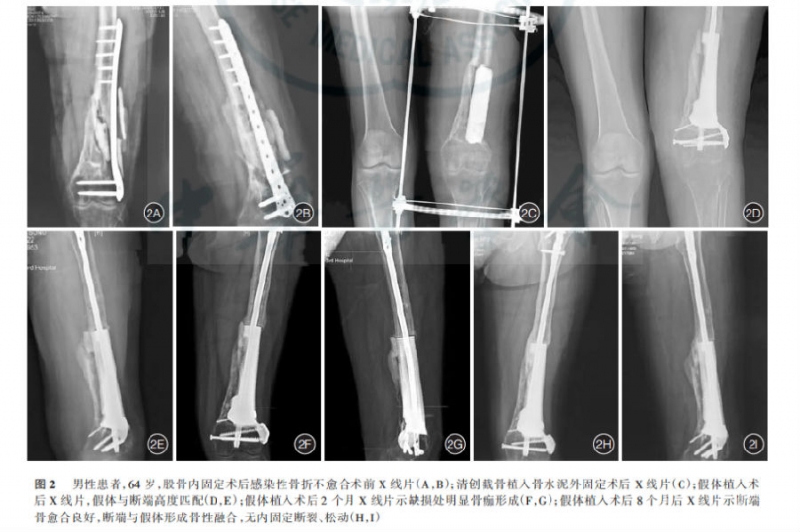

图2: 典型病例

结果:8例患者术后随访6-18个月(平均12.6个月)。8例患者感染灶控制,无体温升高,窦道愈合,感染指标均在正常范围内,血常规、ESR、C-反应蛋白及PCT,3次以上化验结果正常,连续3次留取引流液细菌培养阴性,随访无复发。

患者从第一次入院到假体置入完成后出院,总治疗时间为65-125d(平均91.0d)。第一阶段局部感染控制及临时稳定重建接受治疗时间13-57d(平均28.7d),第二阶段假体及稳定模式设计用时30-87d(平均48.3d),第三阶段假体与骨之间生物学稳定及融合所需时间28-34d(平均63.0d),无内固定物松动及断裂。7例患者在假体置入术后14.7d(4-42d)恢复完全负重活动,1例患者因有严重骨质疏松症术后6个月恢复完全负重。8例患者术后关节功能恢复良好。